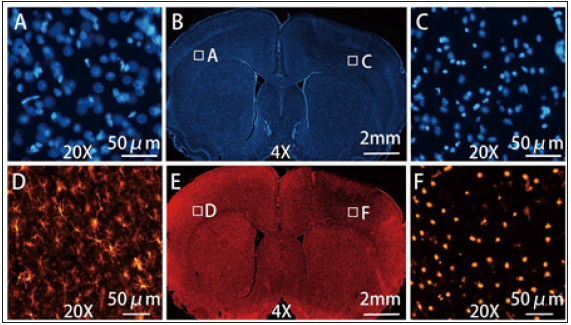

The Nissl-stained slices were examined under light-microscopy and revealed an edematous area extending through the cortex towards the subcortical corpus callosum and the lateral ventricle in a cone-shaped manner (Figure 1). There were 8 rats which presented with discrete hemorrhages within the brain parenchyma under the stimulation site (Figure 1). In the lesion area, there was increased extracellular space and shrunken cells in contrast to the normal tissue (Figure 2). All lesions showed severe damage and the neurons were markedly shrunken and dark in all grey layers and white matter. The columnar organization of neurons were disrupted in all layers. DAPI staining showed some nuclei were deformed (Figure 3). IBA-1 staining of microglia on the control side showed a ramified morphology. In contrast, most microglial under the stimulation site exhibited a dense, spherical morphology (Figure 3).

Figure 3: The morphological changes of cells observed through DAPI and IBA-1 staining of stimulation side and contralateral side. The DAPI staining (B) showed normal cell nucleus of the control side (A) (20X) and the loosened and deformed nucleus in the lesion (C) (20X). The IBA-1 staining (E) showed ramified (or resting) microglia on the control side (D) (20X) and reactive (or phagocytic) microglia in the lesion (F) (20X).